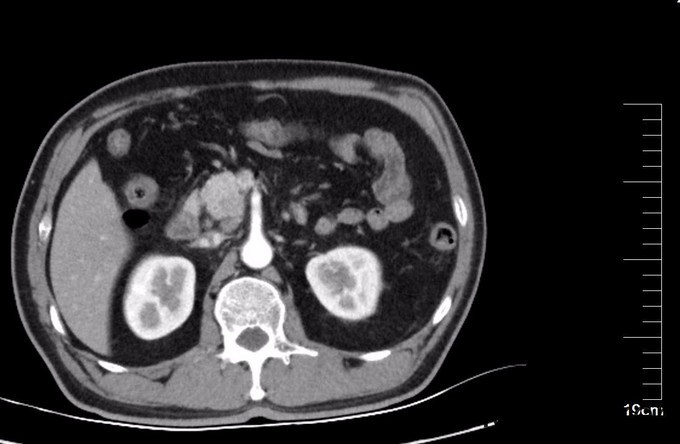

查体:全身皮肤及巩膜黄染,腹部膨隆,无胃肠型,腹软,中上腹压痛,无反跳痛,肝脾未触及,肝肾区无叩痛,肠鸣音6次/分,移动性浊音(-)。 辅查: CT:胰头部隐约见弱强化灶,局部门脉管径变细,胰头周围及腹膜后见增大淋巴结。胆总管胰腺段管壁增厚,明显强化,近端肝内外胆管扩张。胰管未见扩张。胰尾部见小囊状不强化灶,长径约8mm。MR 肝脏表面光滑,各叶比例协调,肝实质信号欠均匀。肝内外胆管普遍扩张,胆总管下段狭窄,中上段扩张,最宽处约1.8cm,胆囊壁增厚,其内信号不均。胰头部见稍长T1稍长T2信号影,境界模糊,范围约2.9cm×1.5cm,胰腺体尾部见长T1长T2信号结节影,大小约8mm×3mm,胰管轻度扩张。脾脏不大。 MRCP:肝内外胆管普遍扩张,胆总管下段狭窄,中上段扩张,宽约1.8cm,胆囊轮廓不清。胰腺体尾部见长T2信号结节影,大小约8mm×3mm,胰管扩张,胰腺头部主胰管狭窄。血清胆红素190.1umol/L,以直接胆红素升高为主。

诊断: 胰头占位 恶性可能大 治疗:全麻下手术探查:肝脏於胆改变,无转移结节,腹壁及盆腔未见癌转移,胰头略增大,切开kocher筋膜,游离十二指肠降段,显露胰头后方,触及胰腺钩突2.5×2.0cm质硬肿物,界不清,胆囊无明显增大,约7×4×3cm,肝总管、胆总管全程明显扩张,直径约1.8cm,术中诊断胰腺头部占位,行胰十二指肠切除术,术中冰冻病理及术后病理证实恶性。病理镜下:癌细胞呈不规则腺样,筛网状排列,部分区域见淋巴组织。胰腺腺癌,高分化,肿物周围见少许淋巴结结构,考虑淋巴结受侵及,胃、肠、网膜未见癌,慢性胆囊炎。CD34及D2-40染色未见明显脉管癌栓,S-100染色见神经侵犯。

术后抑制胰酶,抗炎,补液治疗,检测引流液淀粉酶,最高394U/L, 没有胰瘘。术后复查腹部CT,可见胰腺内置管,脾窝积液,深约1.8厘米,因无明显发热,积液未行穿刺,给予利尿处理。胰腺癌预后差,术后5年生存率低,被称为癌中之王。如果肿瘤位于胰头,由于多数会引起黄疸,因此发现会比胰体尾癌早,因此预后也好于胰体尾癌。诊断此病,EUS,CT,PRCP都有价值,如果在EUS或CT引导下细针穿刺活检,阳性率可达80%。治疗上首选胰头十二指肠切除术或保留幽门的胰头十二指肠切除术,全身化疗用于辅助性治疗和局部晚期无法切除以及有远处转移的胰腺癌病人,常用的药物有吉西他滨,奥沙利铂,氟尿嘧啶,伊立替康等。